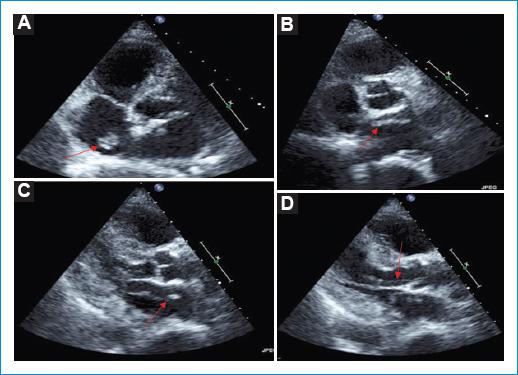

Una vez se trasladó la paciente a la unidad de cuidados agudos cardiológicos se le realizó ecocardiografía transtorácica (ETT), en la que se objetivaron trombos libres en las cavidades derechas, principalmente en la aurícula, y que protruían desde la vena cava inferior (Fig. 1). Se solicitó por este motivo una angiografía por TC con protocolo de TEP, en la que se objetivó TEP masiva bilateral (Fig. 2). Posteriormente, en una nueva ETT de control, se objetivó la presencia de un aneurisma del septo interauricular con aparente protrusión de la masa trombótica a través de este y que se extendía hacia la válvula mitral, y otra masa de aspecto trombótico en el tracto de salida del ventrículo izquierdo y la válvula aórtica (Fig. 3).

Figura 3 A: eje corto de ecocardiografía transtorácica (ETT) que muestra un trombo en la aurícula derecha (flecha). B: eje corto de ETT que muestra un trombo en la aurícula izquierda (flecha). C: eje largo de ETT que muestra un trombo atravesando desde la aurícula izquierda al ventrículo izquierdo (flecha). D: eje largo de ETT que muestra un trombo filiforme a nivel del tracto de salida del ventrículo izquierdo (flecha).